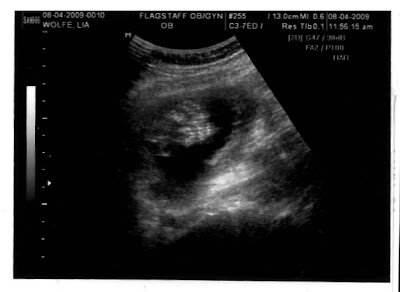

Frontal view, top of head pointing to right

These are 20 week ultrasounds. Pretty sweet. I think these are better than what people got 5 years ago, and this is our third set!